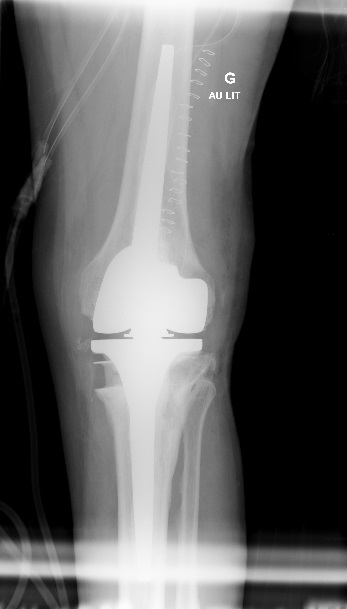

C’est vers le milieu du 20ème siècle que la forme que nous connaissons aux prothèses articulaires actuellement a été fixée. La principale révolution a eu lieu au niveau de la hanche et provient de deux chirurgiens orthopédistes : le Suisse Maurice-Étienne Müller de Berne et le Britannique Sir John Charnley. Ils ont conçu une prothèse articulaire transformant une hanche naturelle qui relie une grosse tête de fémur (pouvant aller de 44 mm à 62 mm) et un cotyle, en une tête métallique de 22 ou 28 mm portée par une tige scellée dans le fémur et articulée avec une cupule en polyéthylène PE (cf. infra) scellée dans le bassin : c’est le concept du Low Friction torque Arthroplasty (LFA), autrement dit le couple de faible friction tribologique. En effet, jusque dans ces années 1960, les prothèses tâchaient de reproduire tout bonnement la hanche naturelle telle quelle. La conséquence est une faible épaisseur de PE dans le cotyle prothésé, or nous n’étions pas encore à l’époque du PE de haute densité comme aujourd’hui. Le résultat est une usure rapide de la cupule en PE (qui est littéralement laminée par la tête prothétique) avec relargage des particules de polyéthylène responsables d’une réaction de la part des cellules de défense de l’organisme aboutissant à un descellement de la prothèse. C’est également au début de ces années 60 que le ciment acrylique a été introduit. C’est du poly méthyl méta acrylate qui, en se polymérisant devient dur et permet de sceller les implants dans l’os. Le prix à payer pour ce modèle de « petite tête fémorale » dans une « petite cupule cotyloïdienne » est l’instabilité avec des luxations. Pour y pallier, des cupules dites rétentives ont été introduites avec comme conséquence, l’augmentation des contraintes sur le PE dont le corollaire est l’usure – descellement. Jusque dans les années 90, la durée de vie des prothèses était autour de 10 ans.

Actuellement, l’amélioration de la qualité des matériaux ainsi que de leur usinage, surtout le polissage de la surface de friction, ont permis de porter la durée de vie des prothèses au-delà de 30 ans. Trois catégories de matériaux sont actuellement utilisées. Il s’agit des alliages métalliques, des céramiques et du polyéthylène de haute densité. Des essais d’implants en carbone sont en cours.

Les alliages métalliques sont essentiellement en chrome – cobalt et en titane. Les céramiques sont des matériaux non métalliques et non organiques obtenus par l’effet de fortes températures sur de l’alumine ou du zircon. Le polyéthylène est un matériau plastique issu de l’industrie pétrochimique. Il sert à constituer la surface de friction des implants. L’introduction du ciment acrylique dans la fixation des implants à l’os date du début des années 60. Depuis le milieu des années 80, le concept de prothèse sans ciment est apparu. Le principe consiste à recouvrir la surface de contact des implants avec l’os d’un revêtement dit ostéo-conducteur. Il s’agit de l’hydroxyapatite, un composant minéral naturel de l’os que l’on produit artificiellement. Au contact de la prothèse, l’os du voisinage identifie cet hydroxyapatite comme un de ses propres constituants et le colonise. La prothèse devient ainsi intégrée à l’os. On parle alors de stabilité secondaire. Naturellement, en attendant cette repousse d’os sur le revêtement d’hydroxyapatite, la stabilité primaire est assurée par l’impaction en force de la prothèse dans l’os et éventuellement fixée par des vis complémentaires. Les couples de friction (surface de frottement des implants) sont de plusieurs sortes : métal – PE, céramique – PE, céramique – céramique. Le couple métal – métal dit de gros diamètre a été utilisé au moins durant trois périodes depuis le 20ème siècle dont la dernière au-début des années 2000 avant d’être à nouveau abandonné pour cause de relargage excessif de particules de métal dans l’organisme.